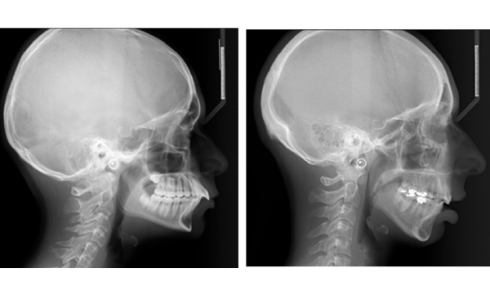

Article réservé à nos abonnés Un traitement orthodontico-chirurgical pour un beau sourire : pourquoi et comment ?

Bien que l’orthodontiste reste le cœur du cabinet, ses assistant(e)s ne sont pas moins concerné(e)s dans leur rôle actif sur...